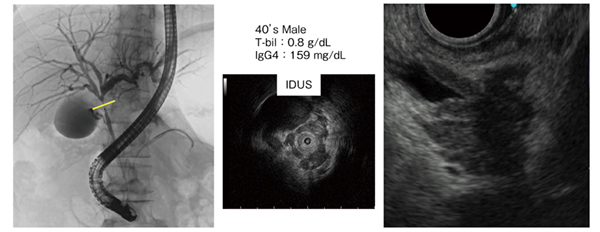

●症例2:肝門部領域胆道がん(40歳代、男性)(図3)

本症例は、狭窄が強いにもかかわらずビリルビン値は0.8g/dLと低く、一方でIgG4値は159mg/dLとやや高値であった。また、IDUSでは上皮性の所見は乏しく、上皮性腫瘍ではないと思われた。本症例はカニュレーションが難しく、生検鉗子を挿入すると膵炎が生じる懸念があり、また、リンパ腫が疑われたため、経乳頭的生検を行わずEUS-FNAを施行した。その結果、リンパ球浸潤はあったものの悪性所見は見られず、黄疸症状もなかったことから経過観察とした。しかし、1か月後に黄疸症状が現れ、ERCPを行ったところ、狭窄の悪化が確認された。生検では2検体採取し、いずれも悪性所見は見られなかったが、画像所見からIgG4-SCとは考えられなかったため、外科手術を行ったところ、低分化腺癌で病期はpT2a(SS)であり、胆道がんの診断の難しさが実感される症例であると言える。

図3 症例2:肝門部領域胆道がん(40歳代、男性)